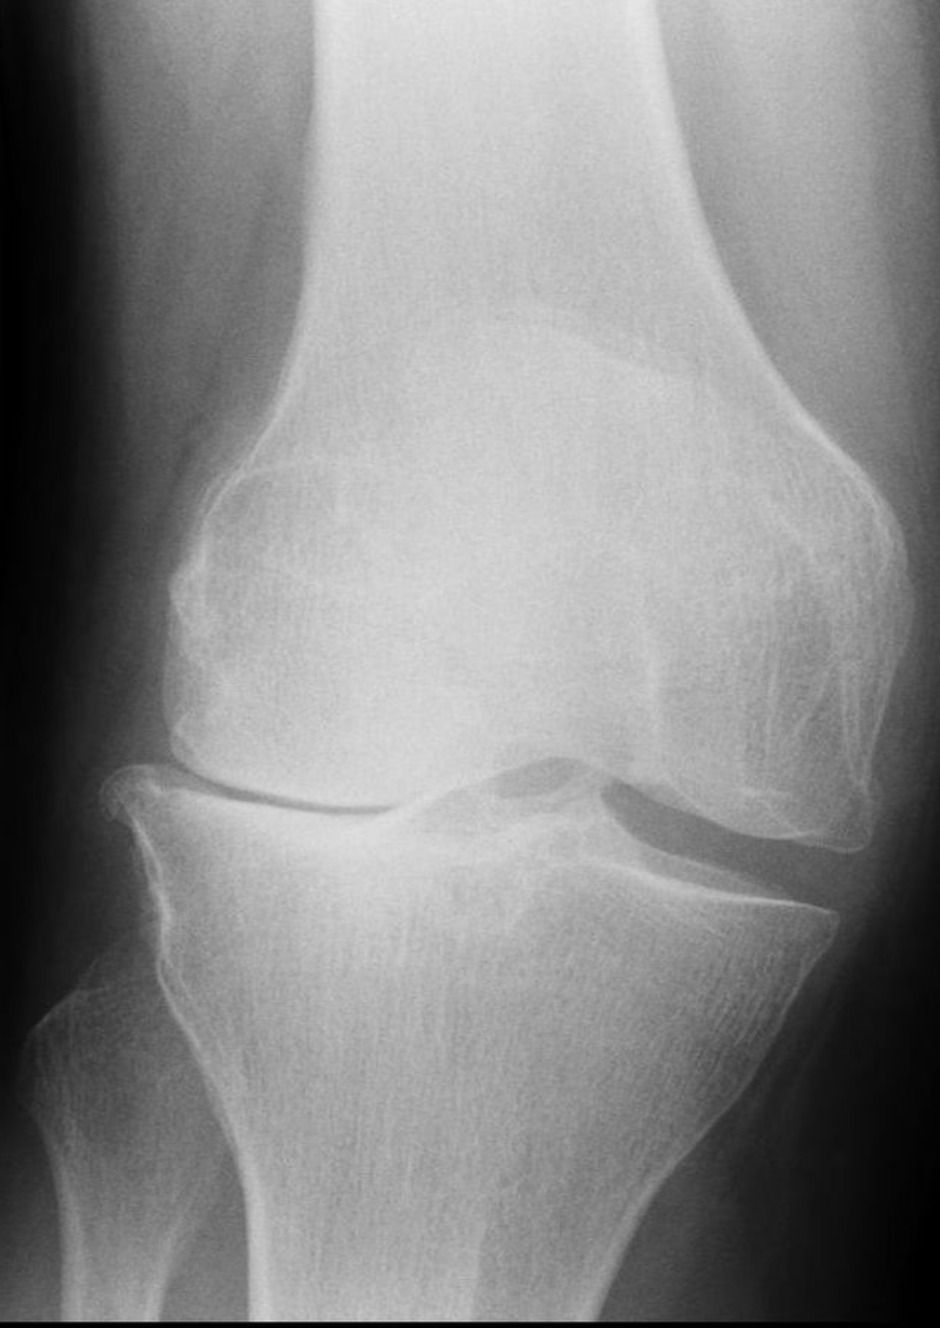

media 1